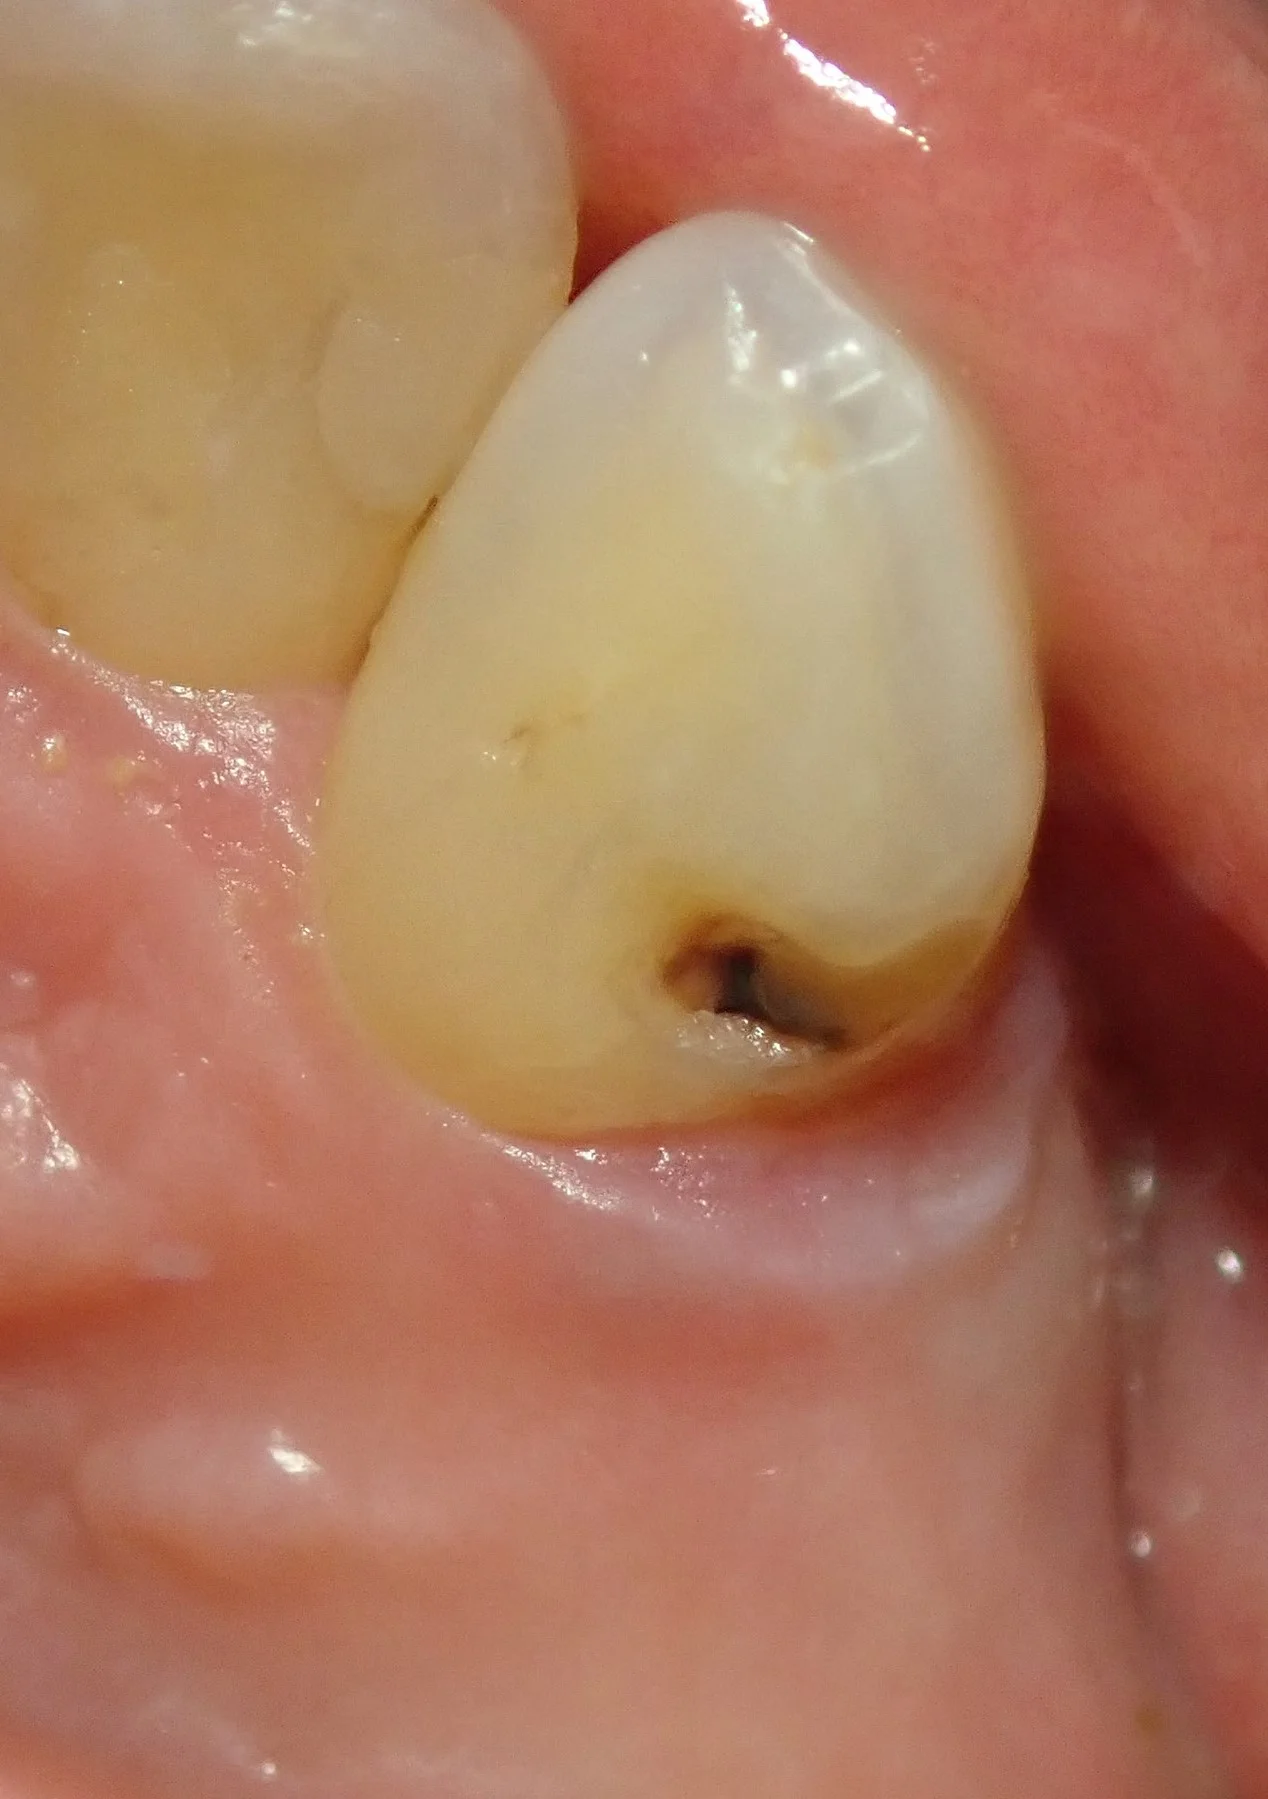

例えば、毎食後に入れ歯を外してしっかりと磨くなどのケアを怠ると・・・

入れ歯の下でこんな感じに虫歯が出来てしまいます。

で、虫歯を取りきったのがこちらです。

地味に神経が軽く透ける程度には深くまで入ってましたね。